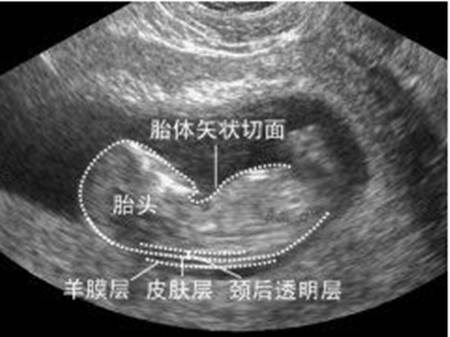

“NT”即nuchal translucency的缩写,中文翻译是“颈项透明带”,是指胎儿颈部的一个透明的液体带。11周之前,NT还没有完全形成。而14周之后,NT便逐渐被淋巴系统吸收,变成“颈部褶皱”,也就是医生常说的NF。

NT检查对胎儿体位有严格要求,只有胎儿处于正中正矢位,即脸和鼻子均向上时,NT的测量值才准确。到底啥时完成检查,看胎儿心情。检查了两次,胎宝宝依然不配合,此时已经4点15分,丢妈在医院耗了一小时。楼下车里等着的小伙伴来了3个连环call,从语气中可以听出,她的心情越来越糟。

高建松:NT检查需要在正中矢状切面测量,测量值会更准确。如果胎位实在难以调整,医生也能观察出NT值在正常值、临界值,或是异常。如果是临界值,建议复查。如果NT值异常,建议:1.染色体检查,如无创DNA或羊穿。2.超声复查。